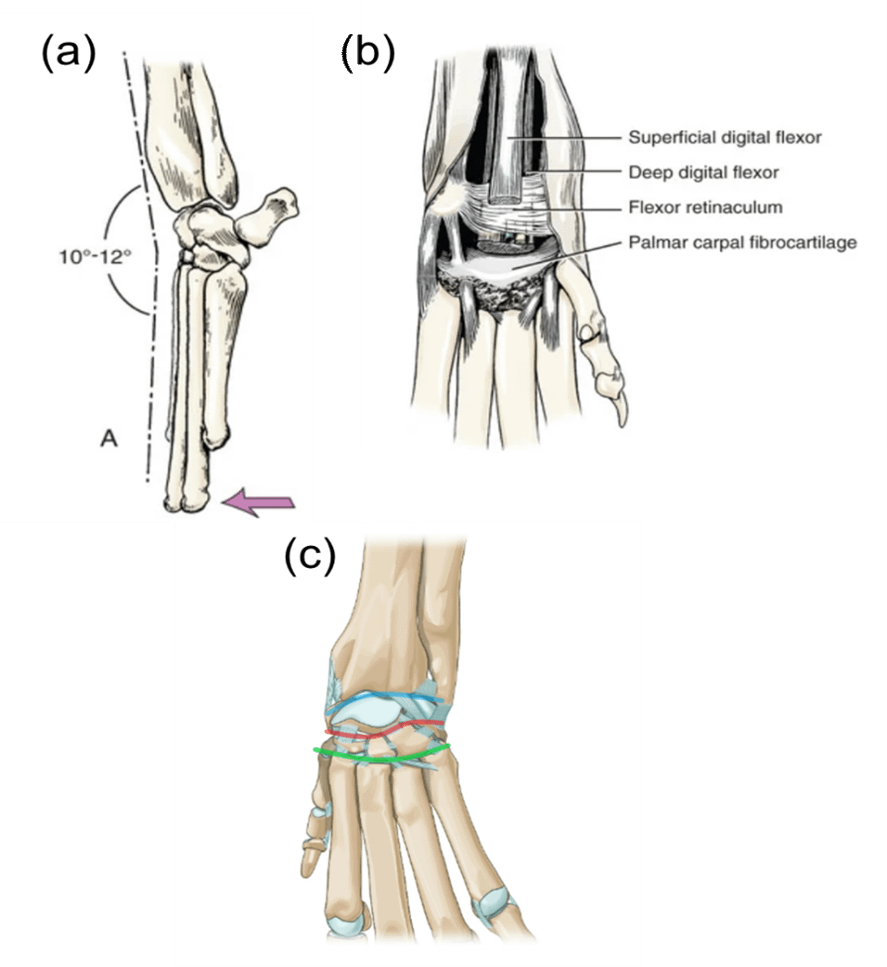

Whilst the anatomy of the dog carpus (wrist joint) has many similarities with humans, one of the main differences is that the maximum range of motion of extension is approximately 10 degrees (Figure 1 (a)) compared to 60-70 degrees in humans. This is due to advanced soft tissue support in the palmar (back) region of the foot, mainly consisting of fibrocartilage and various ligaments and tendons (Figure 1 (b)). The carpus is a complex joint that allows hinge (up down/in out bend and stretch) and pivot (rotation) movements and consists of three joint levels (Figure 1 (c)): the antebrachiocarpal joint (top – blue colour), the middle carpal (middle – red colour) and the carpometacarpal (bottom – green colour) joints. Disruption to the soft tissue supporting structures can occur at any joint level and allows a higher angle of extension due to joint instability, which can lead to further soft tissue damage around the joint, initiate the development of osteoarthritis and be responsible for persistent discomfort and lameness if left unmanaged.

Figure 1